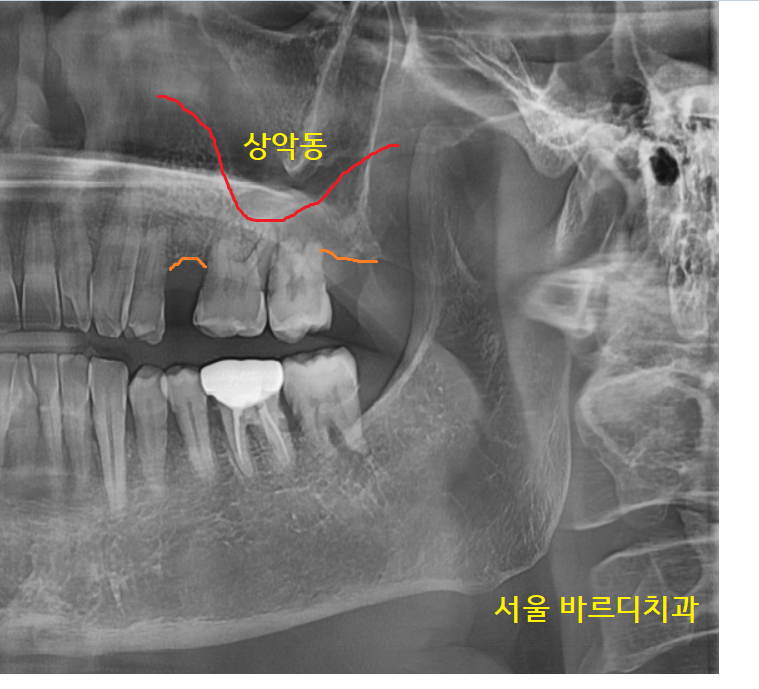

22.12.19

파노라마 상에서 상악동 부위와

치아 뿌리 끝이 엄청 가깝네요~

잇몸뼈가 부족하여 상악동을 들어 올리고

뼈이식을 해야 하는데

상악동 거상술이라 하죠~!